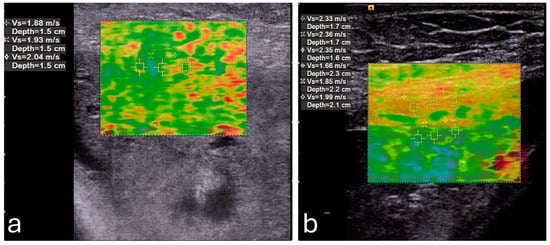

Elasticity in the PFM enables them to respond dynamically to increased abdominal pressure and other physical stresses. For instance, during actions such as the Valsalva maneuver or maximal contraction, the LAM and EAS demonstrate considerable elasticity, which provides resilience against deformation (Figure 3) []. This quality is particularly critical for maintaining the integrity of the pelvic organs and facilitating controlled movement.

Figure 3. Shear wave elastography of the levator ani muscle at rest (a) and during a Valsalva maneuver (b). Image adapted from Gachon et al. [] under a Creative Commons Attribution 4.0 International License. Changes were made to resize and adjust the images.